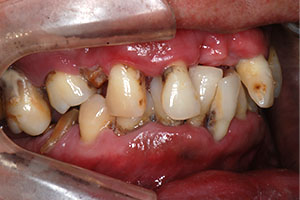

치료증례 전후사진

Before & After